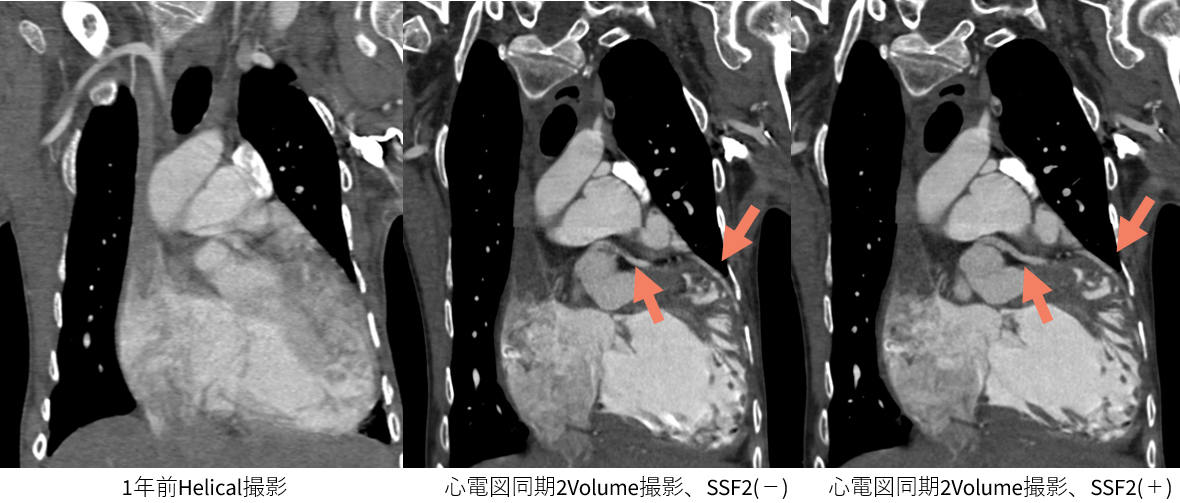

図4 意思疎通困難、呼吸停止不可、20代患者

1年前に管球回転速度0.35[s]にて心電図非同期撮影を行っていた症例。今回、血中の酸素化が悪くなり、A-V Shuntの有無を確認する目的で検査施行。心電図同期を行った上でSSF2を使用。全体の心拍動によるモーションアーチファクトの低減だけでなく、SSF2を使用することで、よりモーションアーチファクトの少ない画像(→)での診断が可能となり詳細な情報の確認を行えます。もちろん冠動脈の評価も十分可能でした。